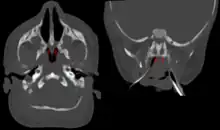

| Bilateral membranous choanal atresia in CT scan | |

Diagnosis is confirmed using CT scan.[1][2] This is also useful for differential diagnosis.[1]